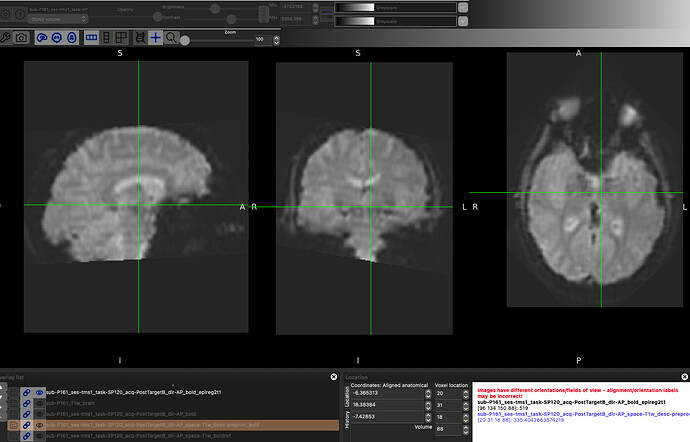

As an example, here is a raw image compared to the fmriprep preprocessing vs a quick epi_reg

Raw:

fmriprep:

epi_reg:

Essentially, I would like to use the epi_reg image as my fmriprep input rather than the raw image, but don’t know how to make that jive using the bids input format.